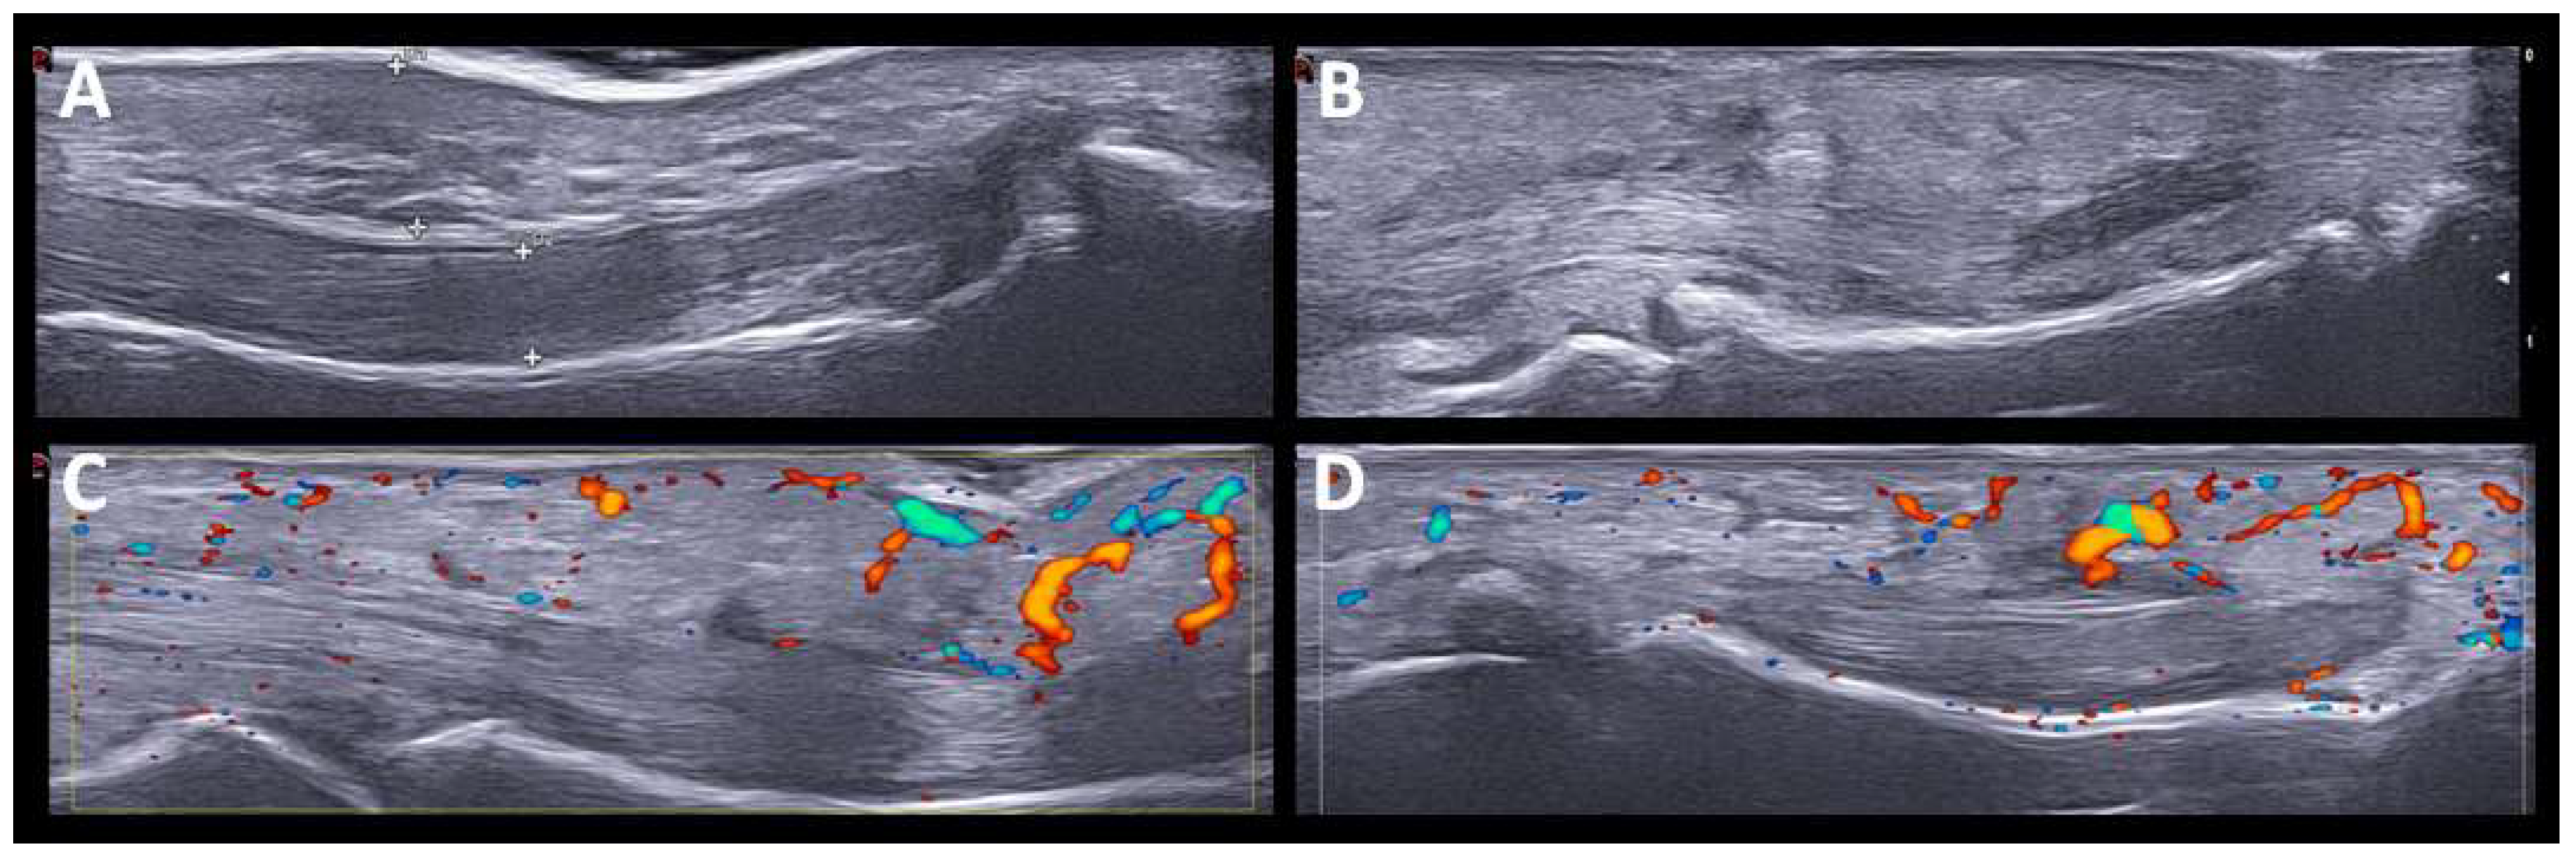

One patient had dactylitis in two fingers. US revealed soft tissue thickening with PD signal, subcutaneous edema, and inflammatory tenosynovitis in the flexors of the hand (Figure 3). The two patients with monoarthritis (carpus and knee) had a history of rheumatic disease (chondrocalcinosis and HLA-B27 associated uveitis). In these patients, SH and grade 2 PD signals were detected. The distribution of joint involvement (synovitis and tenosynovitis) according to the arthritis patterns after US evaluation is shown in (Figure 4).

Figure 3.

US findings in PsA-like pattern. Hand dactylitis. The US findings in PsA-like pattern. Hand dactylitis. The US findings include soft tissue thickening, subcutaneous edema and flexor tenosynovitis (A,B) with Power Doppler signal (C,D).

In particular, in one patient with dactylitis (Figure 3), US findings included soft tissue thickening, subcutaneous edema, flexor tenosynovitis, and synovitis, without major differences with previously-described typical PsA [33]. US findings of oligoarthritis and monoarthritis patterns showed high levels of SH and PD signals, with no particularities with respect to inflammatory arthritis.